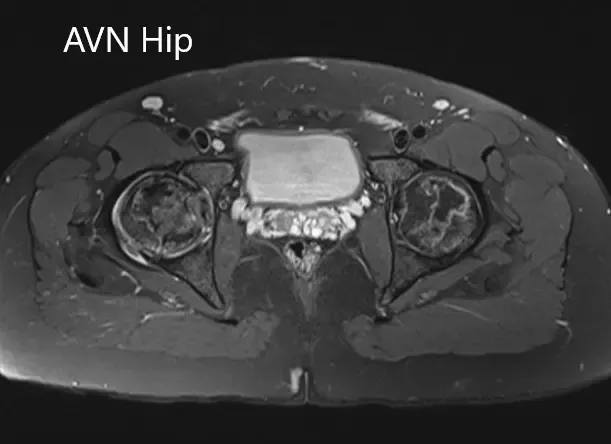

Sección coronal T1WI de la resonancia magnética que muestra AVN en cadera.

Sección coronal T2WI de la resonancia magnética que muestra AVN de cadera.

Secciones axiales de la T2WI y T1WI de la MRI.

Había zonas hipointensas tanto en T1WI como T2WI en ambas cabezas del fémur, sugestivas de esclerosis. Había edema de médula ósea circundante y la zona necrótica bilateral era aproximadamente del 70%.